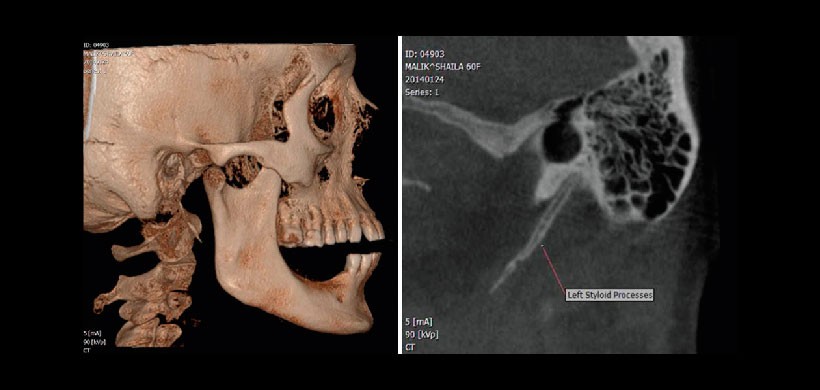

Fig 1 (A y B). Tomografía volumétrica de haz cónico y renderizado 3 D de una paciente femenina de 60 años quien refiere dolor preauricular desde hace 6 meses. El diagnóstico inicial fue de trastorno temporomandibular. Sin embargo el dolor se agrava a la rotación del cuello hacia el lado izquierdo. La tomografía muestra la mineralización segmentada del proceso estilohideo del lado izquierdo.